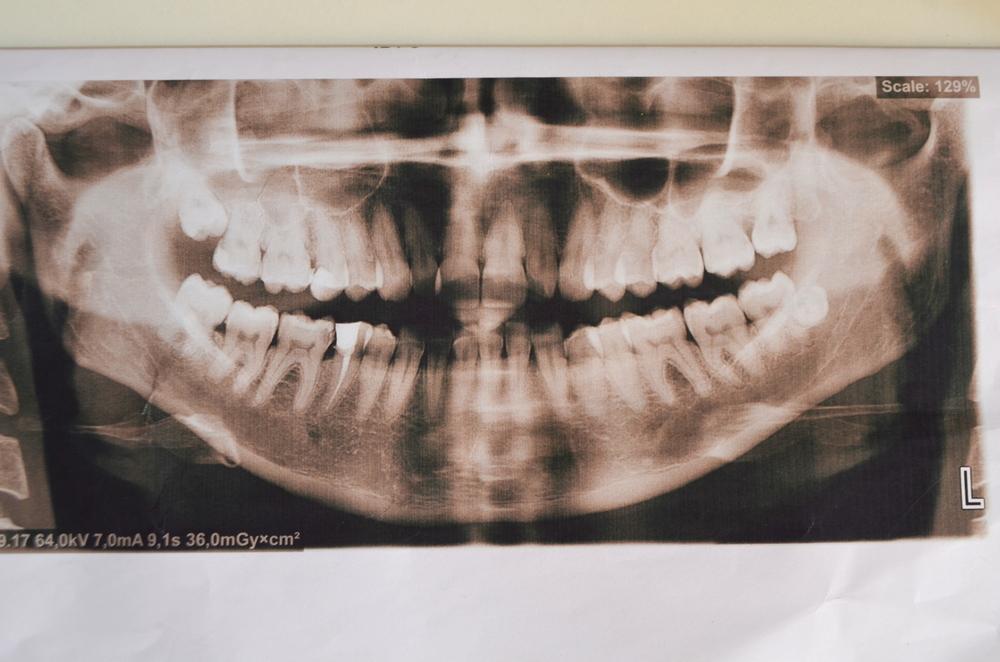

Nha sĩ sẽ chẩn đoán chứng tăng răng bằng cách kiểm tra răng miệng. Đồng thời, bạn cũng được chỉ định chụp X-quang hằm mặt để kiểm tra xem có chiếc răng thừa nào còn mọc ngầm hay không.

Việc điều trị phụ thuộc vào việc răng thừa có dễ gây biến chứng hay không. Thông thường, răng thừa không gây ra triệu chứng gì. Một người có thể không biết rằng họ có răng thừa và chỉ vô tình phát hiện khi đi khám răng hàm mặt khi nha sĩ chỉ định chụp X-quang.